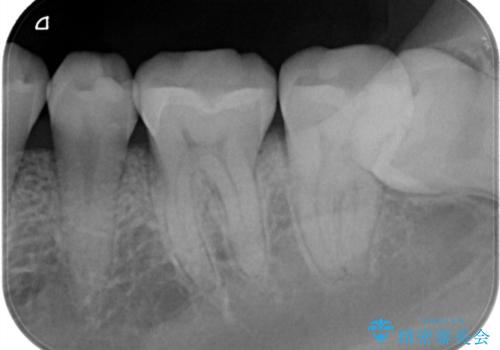

定期検診で虫歯発見。セラミック治療

- 定期検診に通われている患者様で虫歯を発見し患者様に話をしたら、治療を進めていきたいとのことだったので治療を行いました。

まずは虫歯をしっかりと取る事が大切です。

虫歯をとった後は、削った形に型を取る事で隙間なく歯にあった被せ物ができてきます。